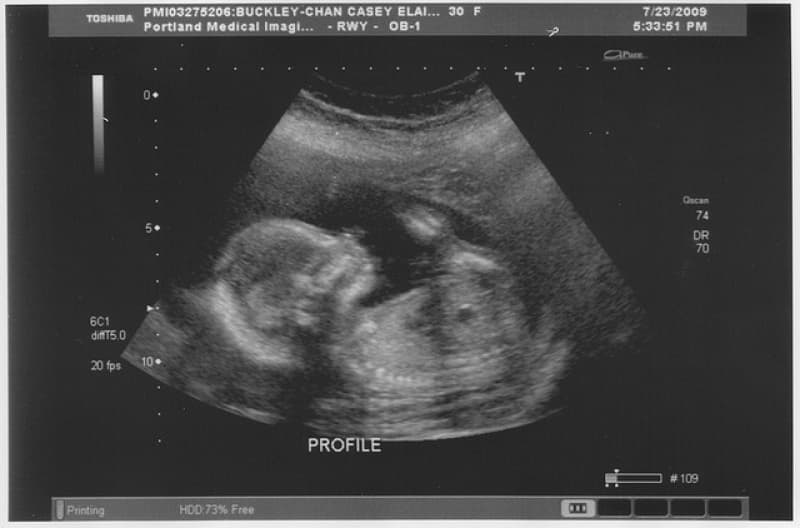

Image: Benjamin Chan on Flickr.